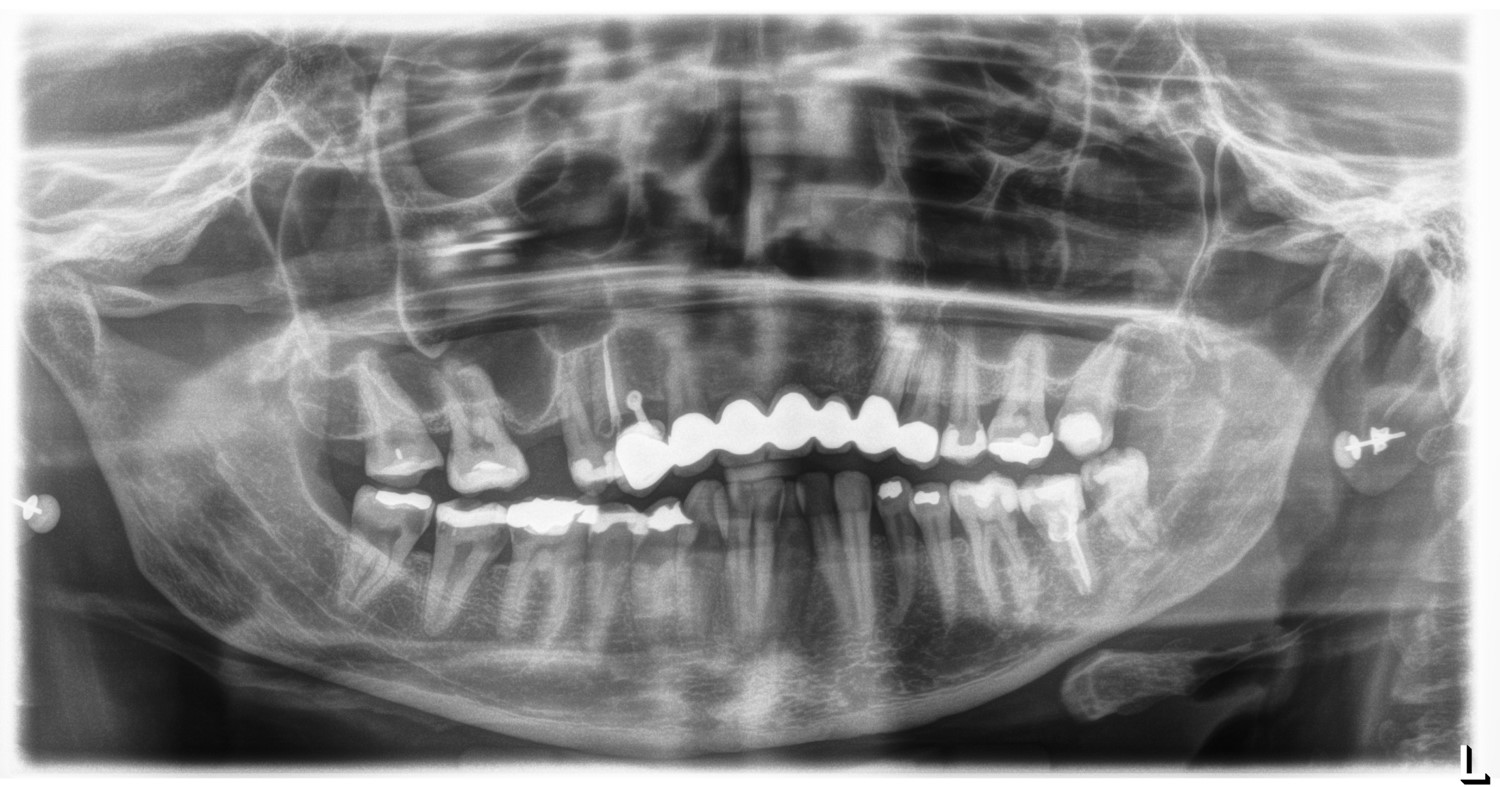

Severe periimplantitis at tooth 15 with bone loss up to 1/3 of the implant